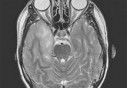

Une caravane médico-chirurgicale nationale destinée aux enfants atteints d’infirmité cérébrale est arrivée samedi à l’établissement public hospitalier Meslem Tayeb de Mascara.